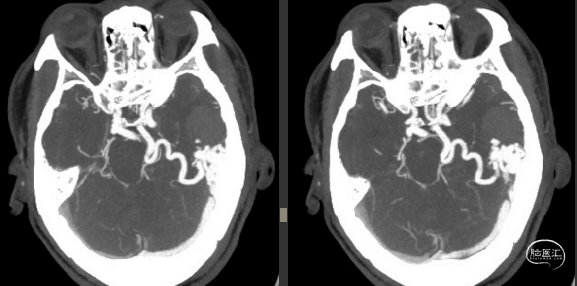

2022-10-28头颅CTA

2022-10-28 神经外科 急诊显微手术

阻断主供血动脉:左侧大脑后动脉分支

清除血肿,阻断大脑中动脉分支、脑膜支后,尝试阻断引流静脉,畸形团立即出血

探查静脉瘤、静脉湖底面折返的供血动脉

最后阻断引流静脉,畸形团干瘪